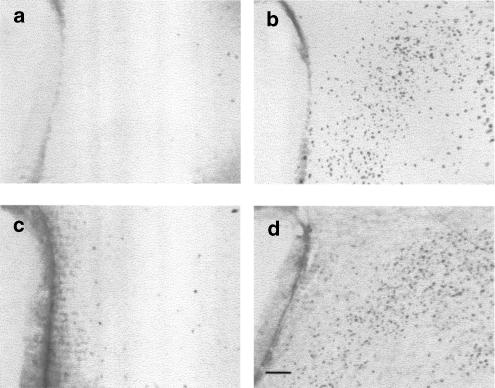

The effect of i.p. 2-DOG on hypothalamic c-Fos immunostaining in fed rats is illustrated in Figure 3. 2-DOG was administered 60 min before the lights were off and 60 min after administration of vehicle, SR-27,897 (0.3 mg kg−1) or L-365,260 (1 mg kg−1). Treatment with 2-DOG (Figure 3b) led to a significant increase of c-Fos expression in PVN, which was not detectable in animals previously treated with the CCK1R antagonist SR-27,897 (Figure 3c) (F(3,8)=186.4, P<0.01). In contrast, the CCK2R antagonist L-365,260 was without effect (Figure 3d). In the parvocellular area, the CCK1 receptor antagonist also prevented the effect of 2-DOG (F(3,8)=113.3, P<0.01; P<0.01 between 2-DOG and 2-DOG+SR-27,897 groups, Newman–Keuls test). Under the same conditions, the CCK2R antagonist L-365,260 (1 mg kg−1) was without effect (Table 4 ).

Figure 3.

c-Fos expression on the hypothalamic PVN of fed rats treated with (a) vehicle, (b) 2-DOG, (c) 0.3 mg kg−1 of SR-27,897+2-DOG and (d) 1 mg kg−1 of L-365,260+2-DOG. Scale bar corresponds to 100 μm.